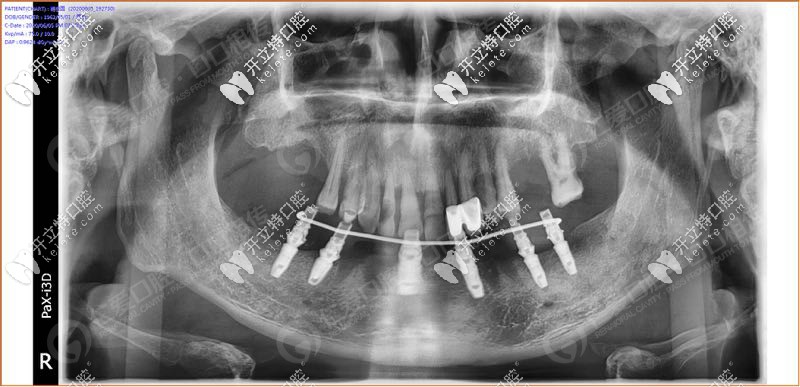

經(jīng)過(guò)我院種植醫(yī)生面診,拍片檢查發(fā)現(xiàn),31、32 、33、 34顆牙松動(dòng)(3度),43顆牙也松動(dòng)了, 44、45多年前做了烤瓷牙修復(fù),其余牙缺失。

具體設(shè)計(jì)方案:拔除下半口松動(dòng)牙后,在33、34、36、43、44、46牙窩采用種植導(dǎo)板植入性?xún)r(jià)比高的登騰種植體,當(dāng)天帶上牙冠,實(shí)現(xiàn)“當(dāng)天種牙,當(dāng)天用”。

手術(shù)時(shí),我院采用的種植導(dǎo)板技術(shù),術(shù)前設(shè)計(jì),種植體植入方向、位置、角度、深度等一目了然,導(dǎo)板輔助將種植植入到理想位置,有效避開(kāi)神經(jīng)、血管等危險(xiǎn)區(qū)域,同時(shí)也大大縮短手術(shù)時(shí)間,在拔牙窩即拔即種,沒(méi)有切口或切小口,愈合快。

順利植入6顆種植體后,把過(guò)渡性臨時(shí)假牙固定到下頜的種植體上實(shí)現(xiàn)了當(dāng)天種牙,當(dāng)天用的即刻負(fù)重種植牙。